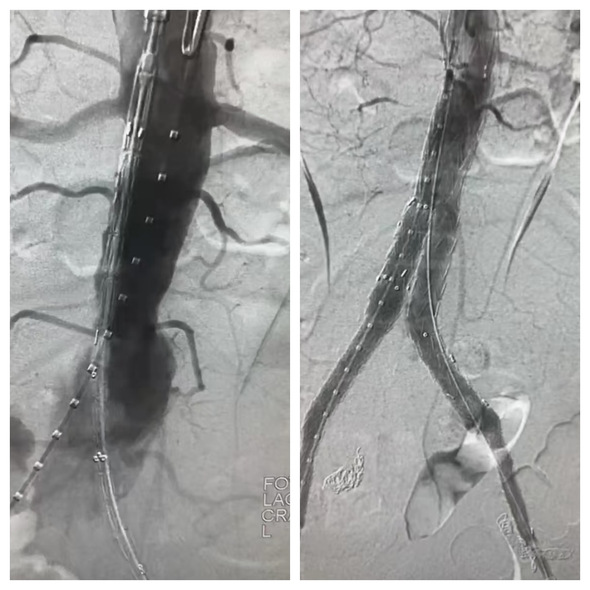

血管外科李喜春主任团队为患者行手术治疗

术中影像